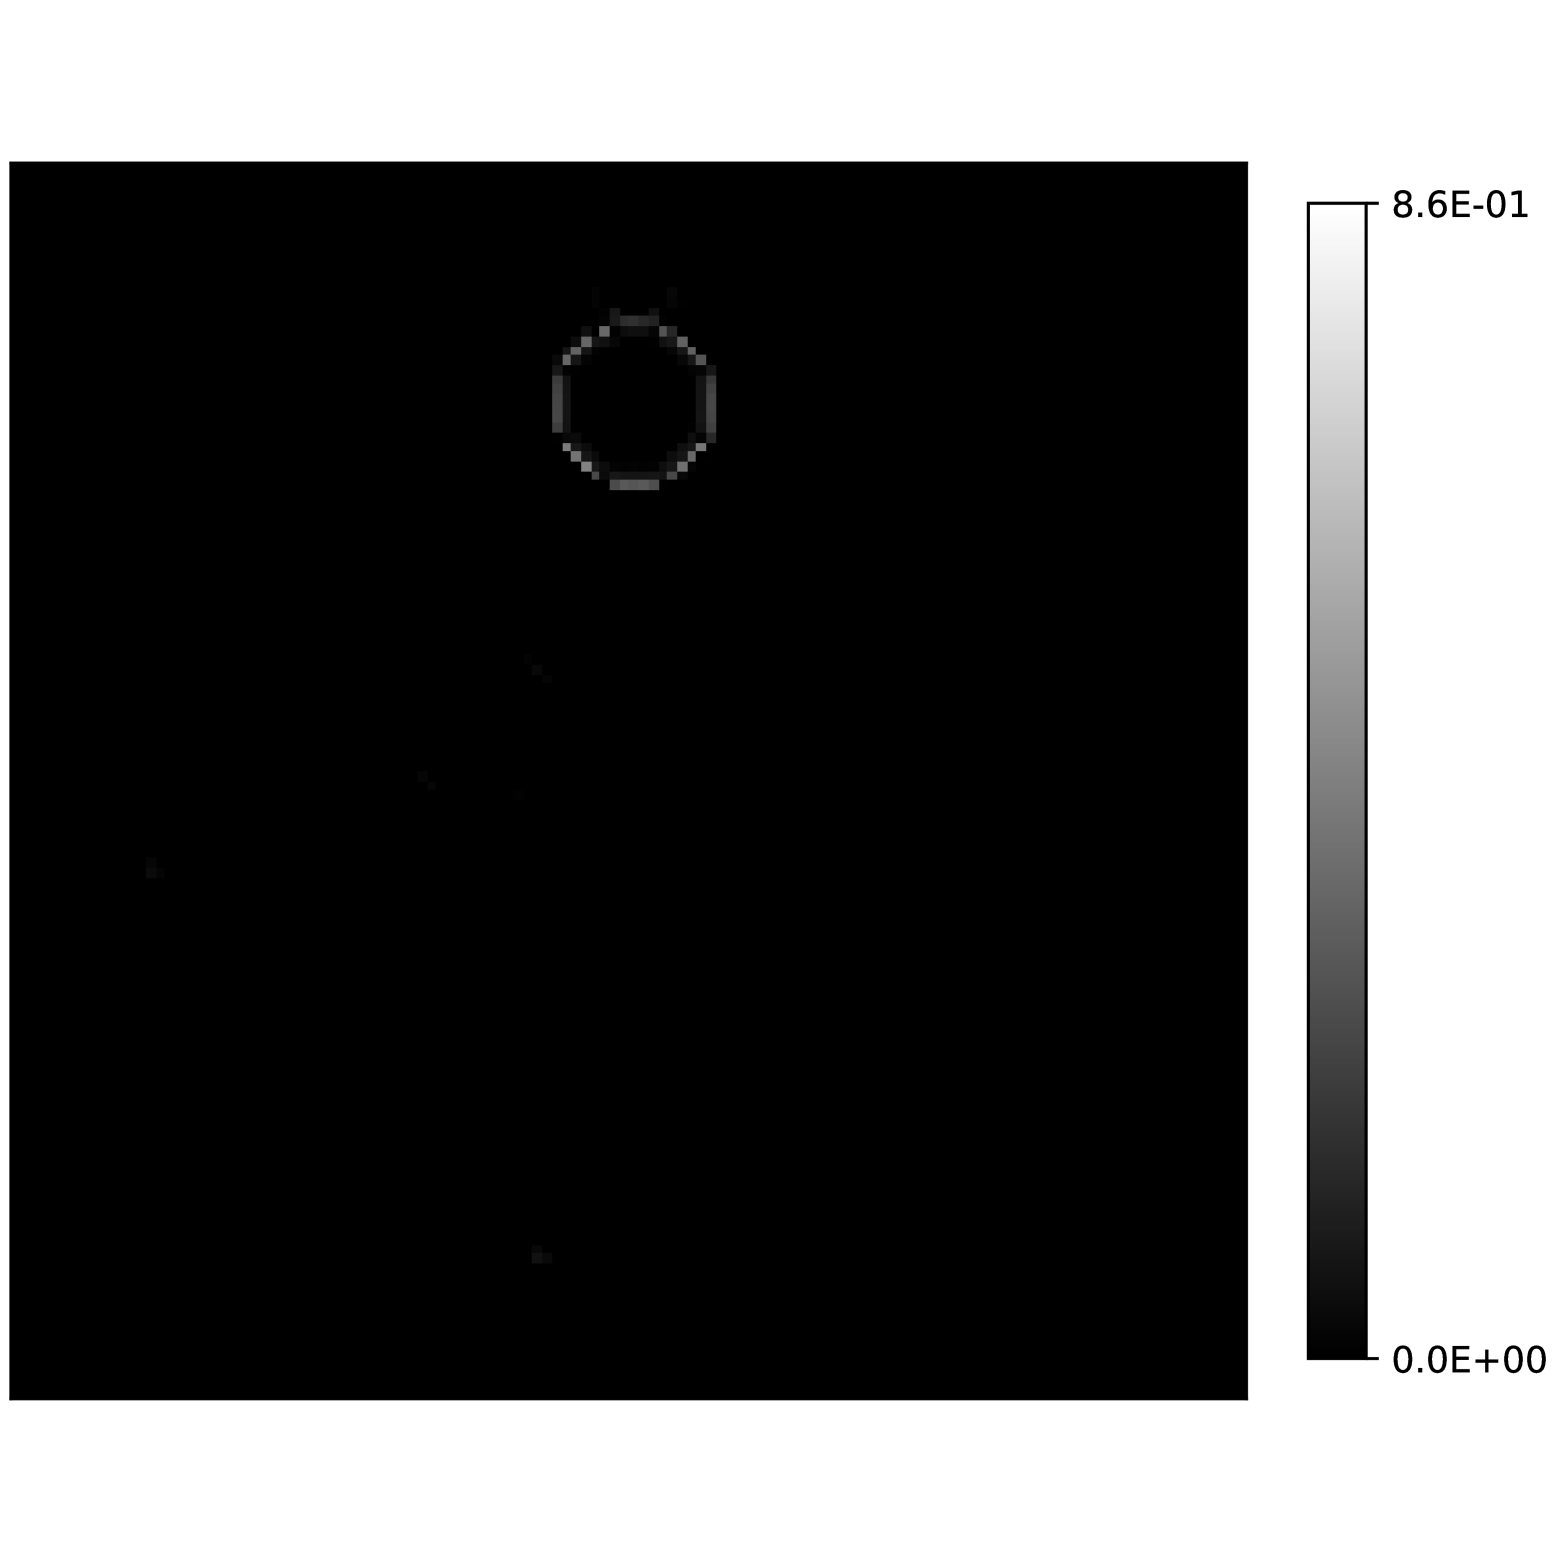

Our theoretical results show that generic concentrations and maps can be recovered exactly even when the fieldmap is not identifiable. To illustrate the impact of this fact, we perform a recovery experiment on a water (Fig. 2(a)), fat (Fig. 2(b)) and silicone (Fig. 2(c)) in silico phantom. The concentrations are all real. The values for the fieldmap and used to generate the signal are shown in Figs. 2(d) and 2(e). The echo times have the form where ms and ms with .

We solve (23) using projected gradient descent as initial iterate a vector with all components equal to one. Forward finite-differences were used to compute the gradient. The bound on the norm of the gradient is Hz at voxels with non-zero signal magnitude, and kHz at voxels with zero signal magnitude. This avoids imposing artificial constraints at voxels with no signal. The step size used is and the termination conditions

In Figs. 2(f), 2(g) and 2(h) show the recovered concentrations of water, fat and silicone, and Fig. 2(j) shows the recovered . These recovered quantities are all qualitatively similar to their true values. In contrast, Fig. 2(i) shows the recovered fieldmap, which differs from its true value. By comparing the errors in the recovered concentrations, we see that they are within a reasonable accuracy except in regions with a large magnitude for the fieldmap gradient, indicating a bound that is too small (Figs. 2(k), 2(l) and 2(m)). A similar behavior is seen in the recovered (Fig. 2(o)). The error for the recovered fieldmap tends to be larger outside the area of the phantom (Fig. 2(n)).